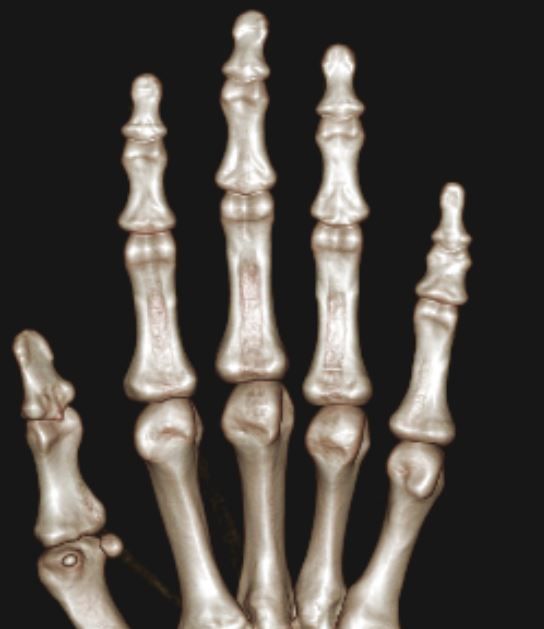

2주전 좌측 3,4수지 손가락이 바깥쪽으로 꺽였습니다.(CT&MRI 사진첨부 했습니다.)

증상은 좌측 제3수지 중지골에 피멍과 통증 그리고 손가락이 안으로 안굽혀 집니다.

골절인지 인대파열인지 아니면 다른 부분이 혹시 보이는지 알려주시면 감사하겠습니다.

• 3번 째 사진

volar plate라는 부분 손상이 의심되기는 하나 이게 명확한 진단은 아니네요. 이런경우는 정형외과 선생님의 임상 진단과 같이 결부해서 골절에 준해서 치료를 어떻게 할지 결정하게 됩니다. 필요하면 손가락 splint 착용하면서 경과를 보실 수 있으니 병원 진료대로 따라 가심이 좋겠습니다.